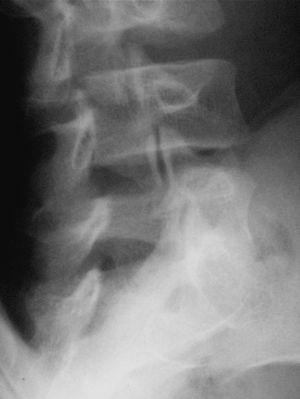

En la visita següent el pacient es presenta amb radiografies que confirmen el diagnòstic d'espondilòlisi L5 unilateral dreta (figs. 1 i 2). D'acord amb el document de consens de la Societat Catalana de Medicina de l'Esport, se sol·licita una gammagrafia òssia planar (GOP) amb tomografia computaritzada per emissió de fotó simple (SPECT). Es decideix continuar amb el mateix tractament i s'assabenta el pacient que serà un tractament a llarg termini.

Figura 2